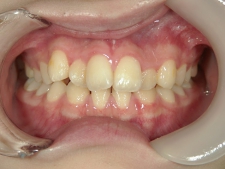

矯正歯科 治療前 正面